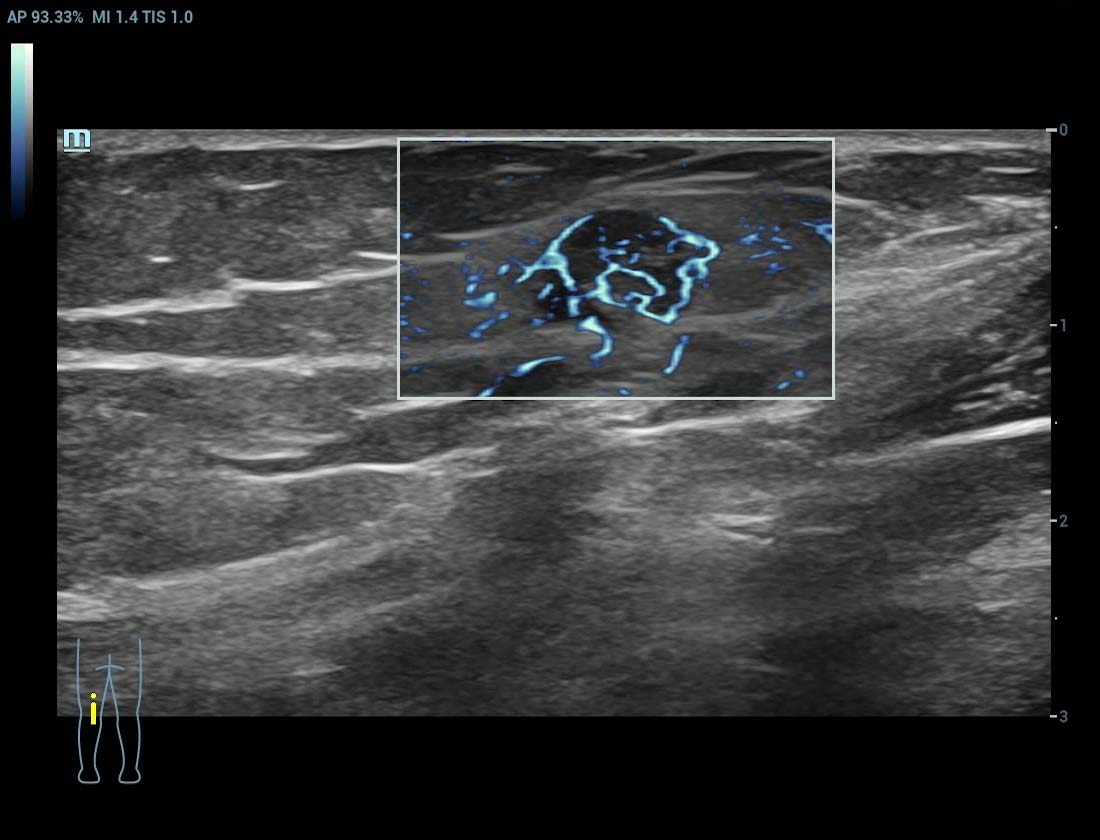

Ultra Micro Angiography (UMA)

UMA migliora la sicurezza diagnostica ampliando la visibilitĂ dei flussi sanguigni fino al livello dei vasi piĂč piccoli, con una sensibilitĂ e una risoluzione superiori.

Massa mammaria pUMA

Tumore alla tiroide sUMA